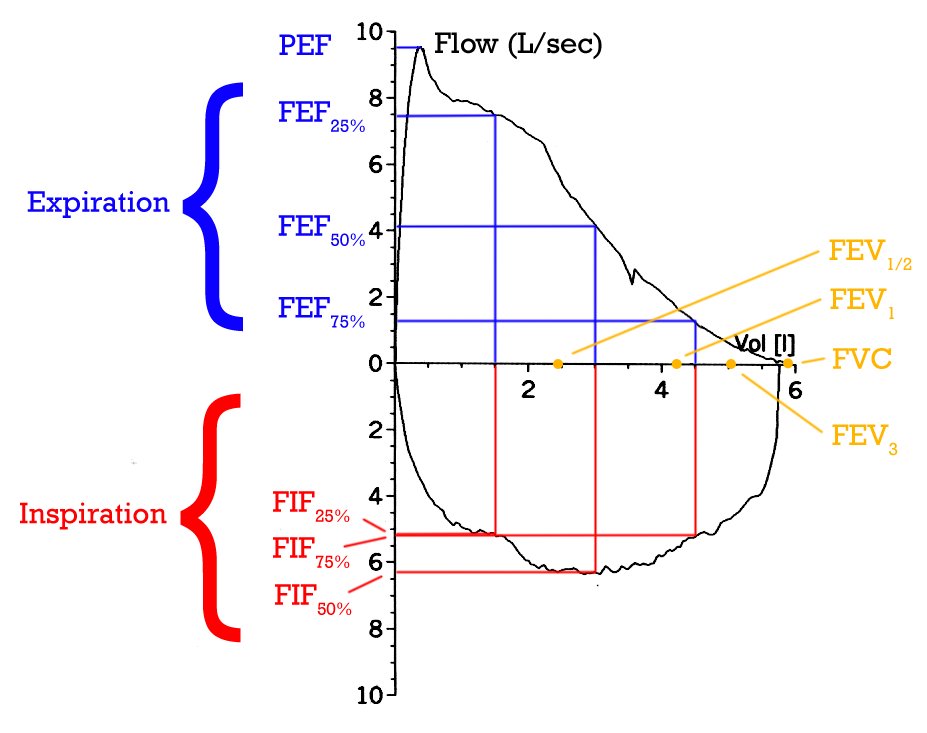

2 – Diagnostic Tools – Spirometry, Arterial Blood gas, Oximeter, Exercise Tolerance Testing, X-ray, Bronchoscopy, Culture and Sensitivity Tests, Sneezing Reflex, Coughing Reflex,

- Peak Expiratory Flow – this test can be done to measure the severity of airway obstruction.